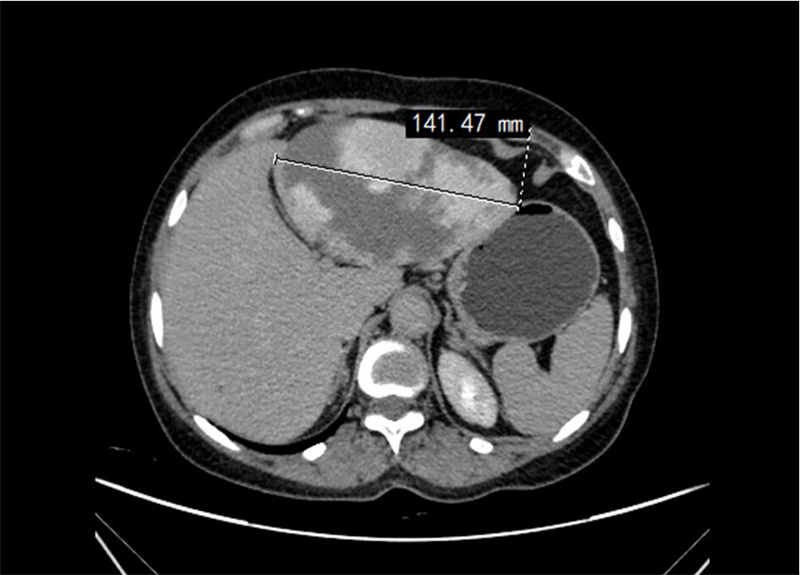

术前腹部CT照片

入院后,经过进一步的详细检查发现,任女士肝脏上的肿瘤为肝血管瘤,体积巨大,压迫了周围的消化道,这是导致任女士持续腹胀症状的主要原因,但好在这是个良性肿瘤。不过由于任女士的血管瘤体积庞大,一旦破裂,后果将不堪设想,可能引发大出血等严重后果,甚至危及生命,需紧急手术治疗。

今年50多岁的任女士近期突感腹胀。起初,她并未将腹胀放在心上,以为只是普通的肠胃不适。但随着时间的推移,任女士少量进食就会导致严重腹胀,而且在肚子上还能摸到隆起的包块,遂赶紧到十堰人医肝胆胰腺外科门诊就诊。然而,初步的检查结果却让在场的所有人大吃一惊:她的肝脏上竟然长出了一个直径约14厘米的巨大肿瘤!面对这突如其来的结果,任女士及其家人陷入焦虑。因情况危急,接诊医生将其收入院接受治疗。